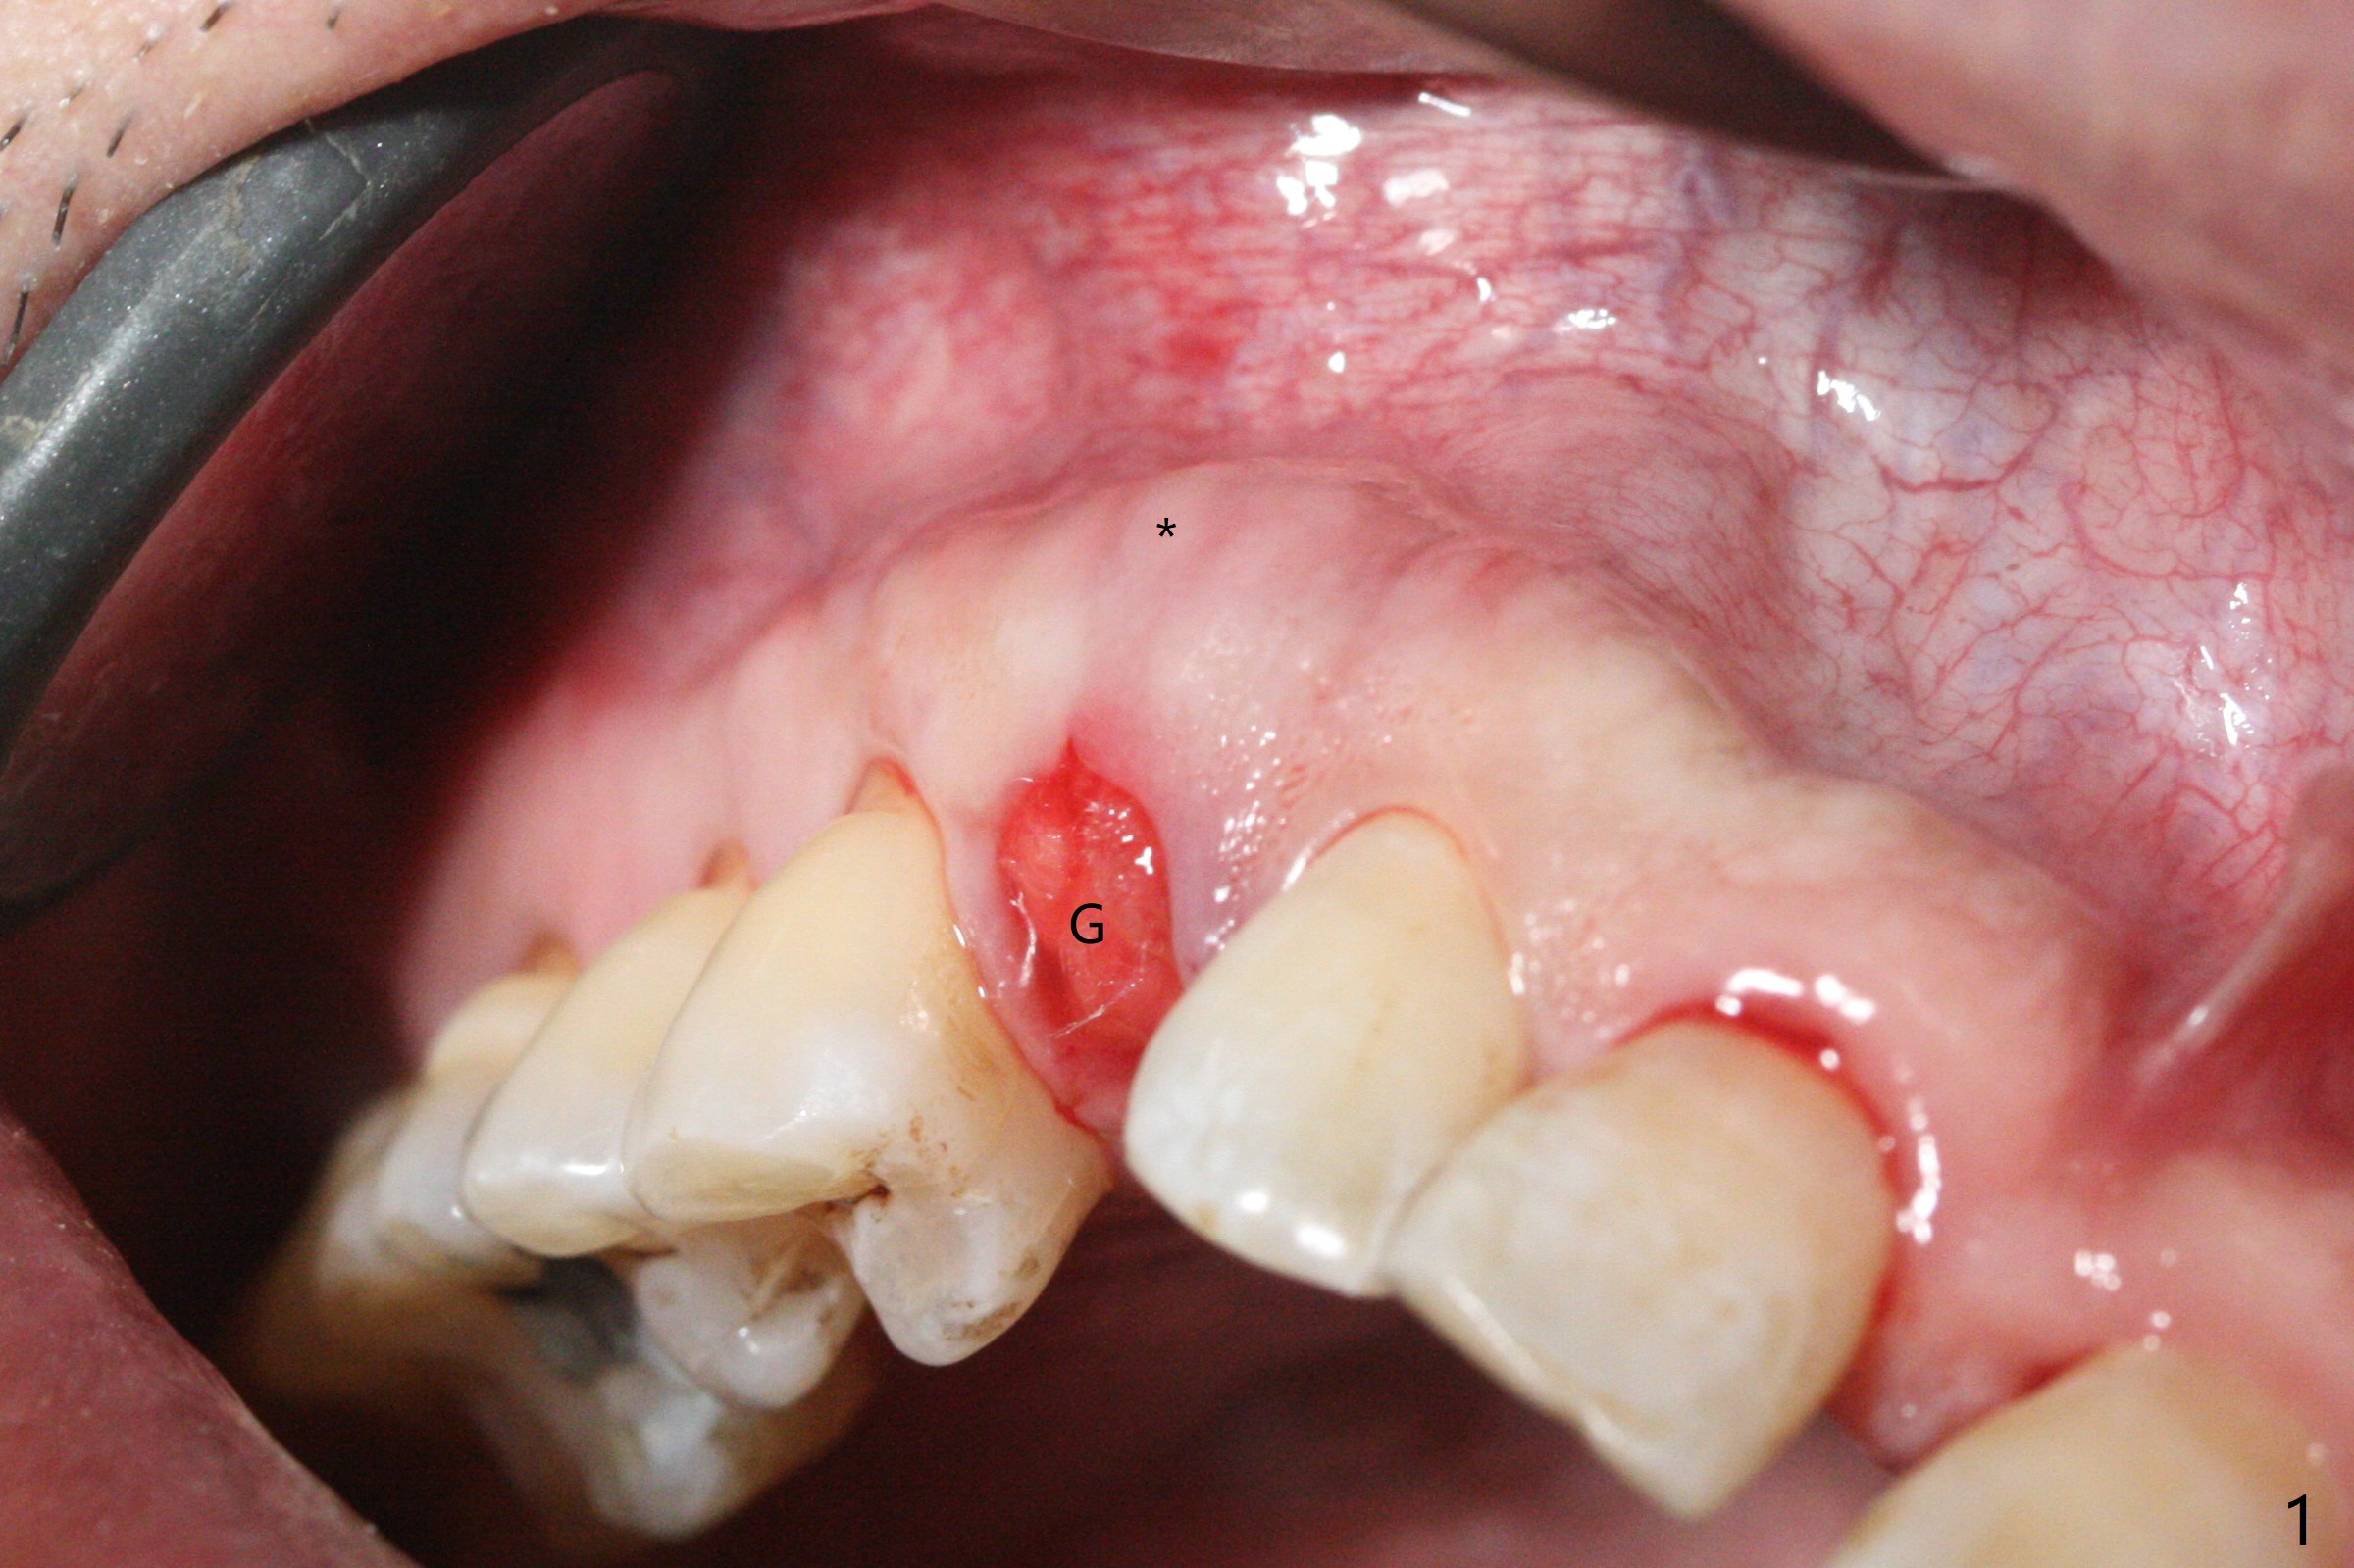

右上乳尖牙拔除后,颊侧尖牙隆起仍旧明显(图一:*(牙槽窝塞入止血纱布)),希望通过导板即种和植入粘性骨粉(图二:*)以及即修,这个局部解剖结构能保留下来。至少术后9天是这样(图三,T: 临时牙冠)。Return to Protect Graft Xin Wei, DDS, PhD, MS 1st edition 05/27/2021, last revision 06/05/2021